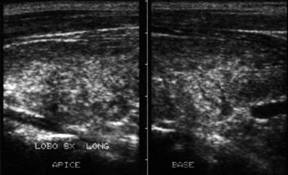

Lob drept in proiectie trasversala si longitudinale.

Lob drept, trasversal si longitudinale.

Lob drept, bazal, trasversal.

Femeie 34 ani. Lesiuni multiple, hipoecogene, difuze,

toti sub un centimetru, in tiroida de dimensiuni normale.

Examen citologic: carcinom papilar.

Examen histologic: carcinom papilar multifocal (4 noduli la dreapta, cu microfocalitati

in stanga ( cel mai mare de 3 mm).